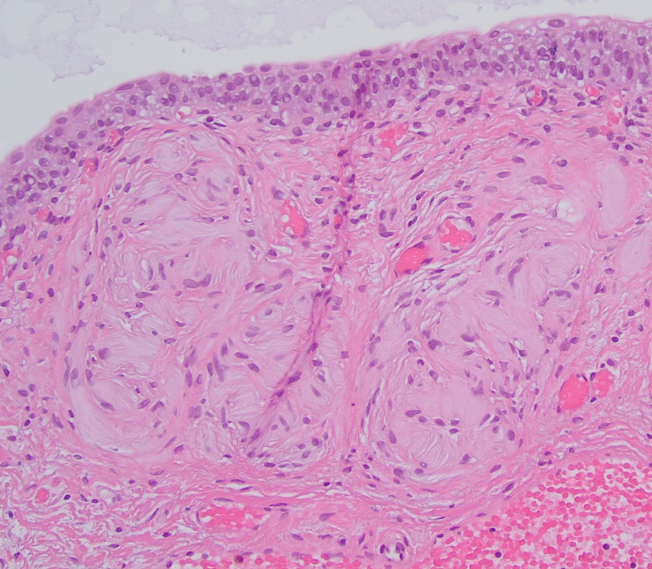

The patient presented with recurrent microhematuria. Cystoscopy revealed diffuse cystic nodules, each measuring approximately 2 mm, scattered throughout the bladder.

Transurethral resection of the lesion revealed a normal urothelial mucosal lining. Within the submucosa, multiple pink, round structures of varying sizes were identified. These structures demonstrated concentric lamellar layers of eosinophilic material, surrounded by Schwannian cells (images 1,2,3). Immunohistochemical stains showed that the cells were positive for S100 (image 4), SOX10, and CD34.